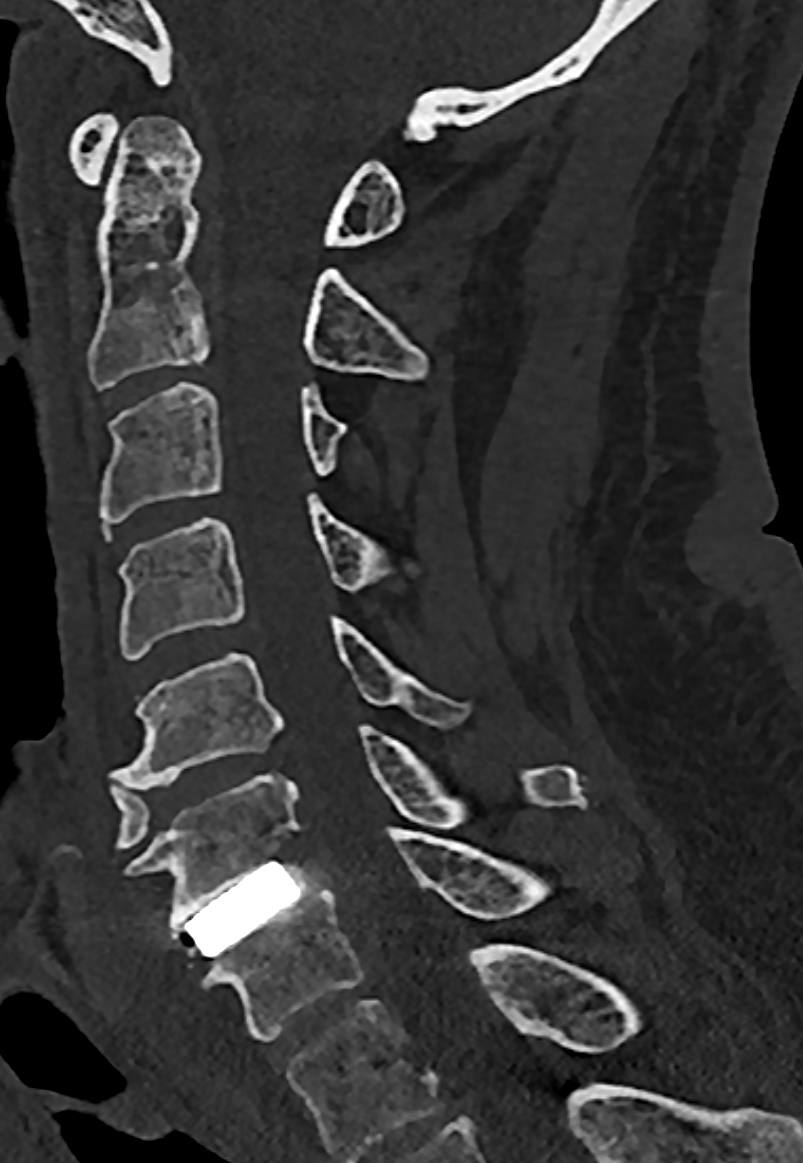

«Первым этапом мы удалили межпозвонковый диск, тотально удалили грыжу. Была выполнена декомпрессия спинного мозга — мы полностью освободили нервную ткань от сдавления. Финальным этапом устанавливается фиксирующее устройство — отечественный межтеловой имплант из сплава титана. Таким образом создаём условия для формирования костного блока, то есть сращения позвонков между собой.